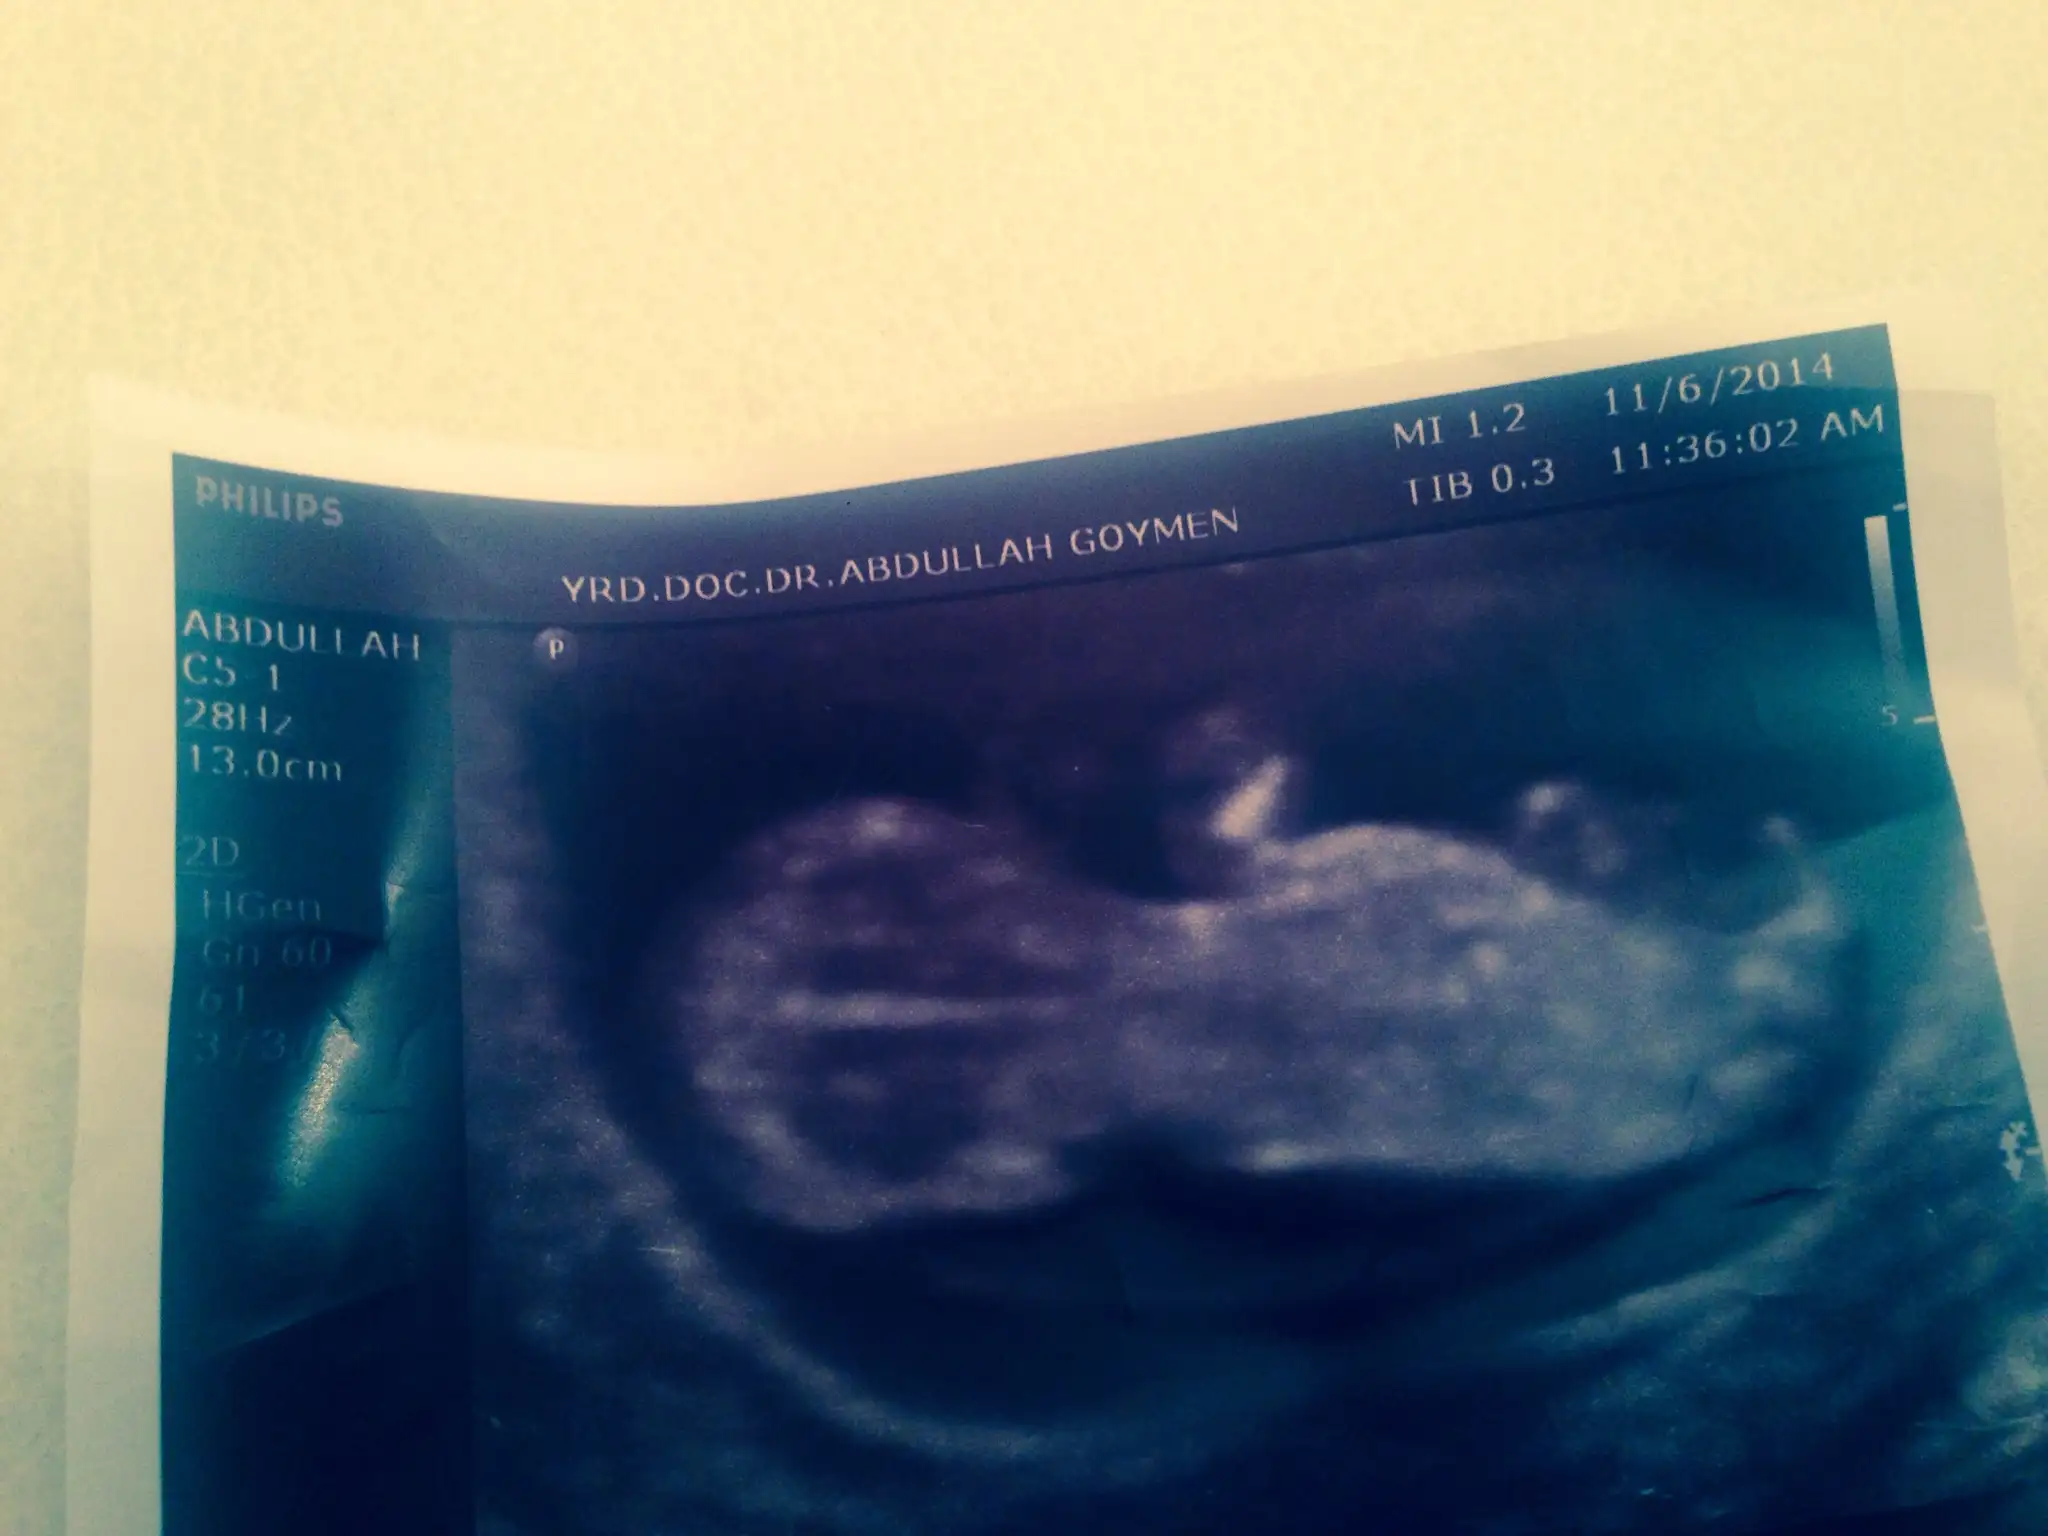

benım bebegım 15 haftalık ama doktor tam net bişi demeyeyim 2 hafta sonra kesin söylerim dedi. ben hiçbişi anlamadm bakınca :) içime erkek doguyor sadece

Eklentiler

erkek gibi ama bilmiyorum genelde 11. hafta net duruyor o zaman ense testi varya daha büyük ultrasyondan bakıyorlar.